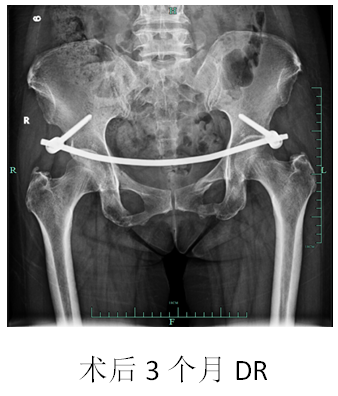

手术用时不到1小时,出血量不足50ml;术中无任何神经血管损伤。术后恢复良好,术后第二天即可坐起,病人及家属对治疗效果非常满意。

目前病人已可离床行走,完成日常生活活动,出院康复休养。

Infix内固定系统,作为近年来国内外针对骨盆骨折设计开发的微创内固定技术,较传统开放手术及外固定架术,具有明显优势:

(1)微创伤口,经皮置入,损伤小,并发症较少;

(2)力臂短、置钉更为牢固;

(3)根据不同骨折类型及骨盆挤压分离情况随意采取撑开或加压固定;既可用于急性期控制骨盆伤情,亦可作为终极治疗手段。

(4)皮内隧道置钉架,极大降低针道感染松动率;

(5)病人舒适度高,便于护理,早期即可坐起、离床活动,生活质量有很大提升。

该技术只要适应症选择正确,对减少手术创伤、提高病人生活质量、加速康复极为有利,是目前骨盆骨折微创治疗中一个极具生命力和应用前景的新兴技术。